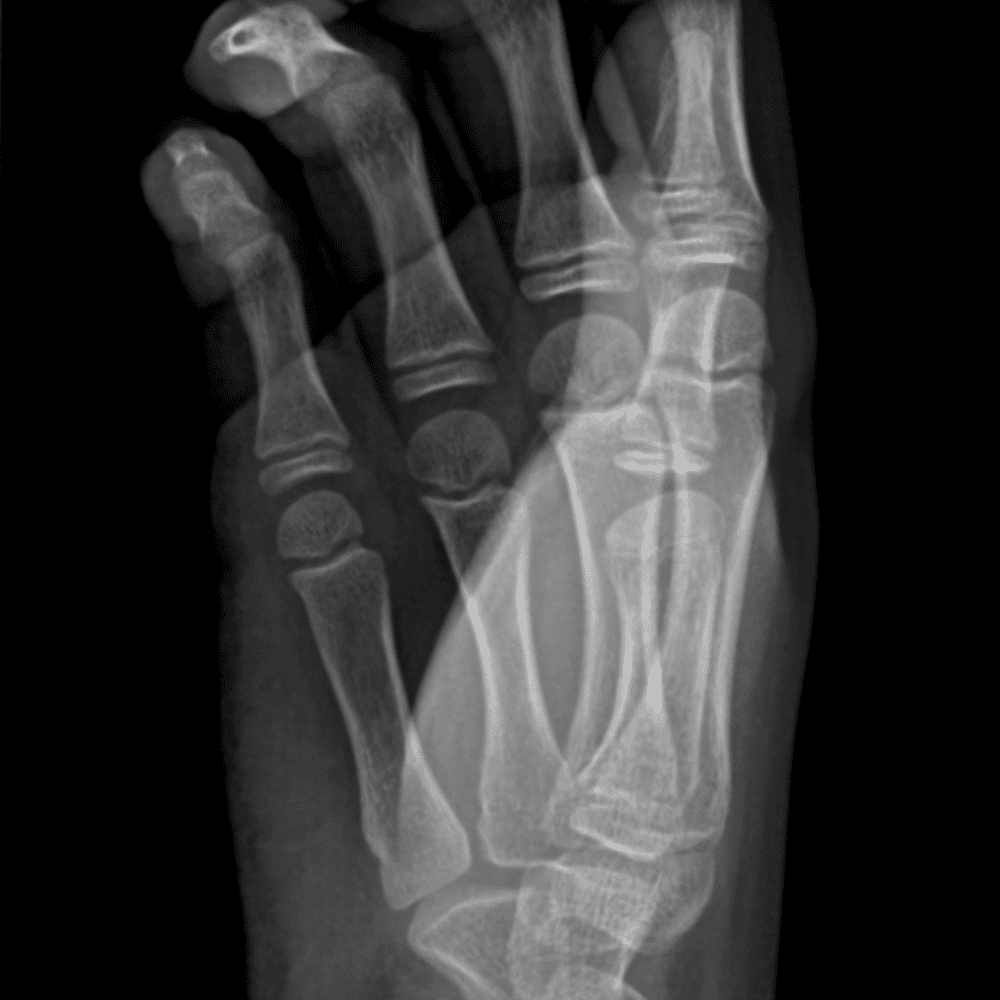

Simulates call by including subtle or difficult cases and some normals.

30 cases